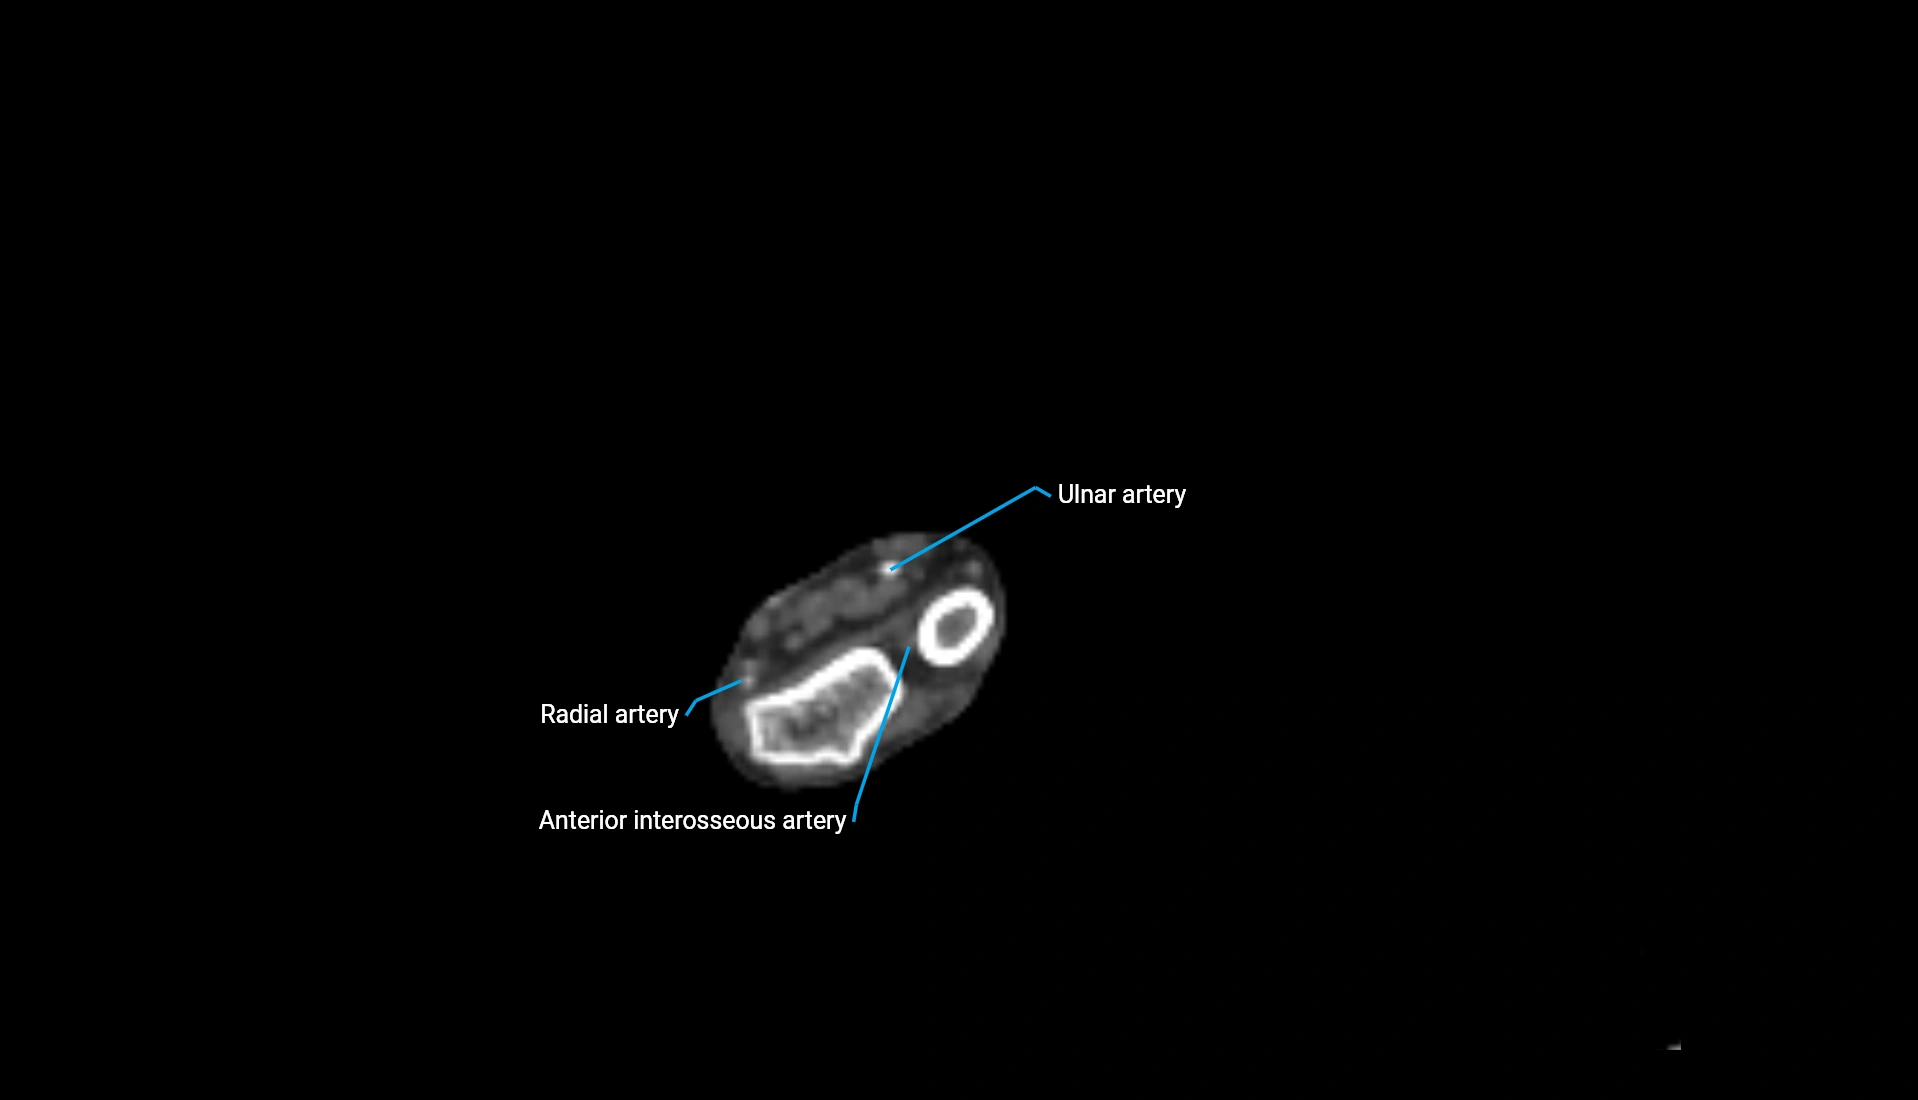

CT Appearance

Non-Contrast CT:

• Cortex: High-density, sharply defined

• Subchondral bone: Dense cancellous matrix

• Articular surface: Smooth concave contour articulating with the capitellum

• Excellent for evaluating bone integrity, alignment, and subtle fractures

Post-Contrast CT:

• Bone: No enhancement

• Joint capsule and synovium: Mild enhancement outlining the joint

• Improves contrast between soft tissues and bony margins

• Useful in detecting subtle joint abnormalities or postoperative changes